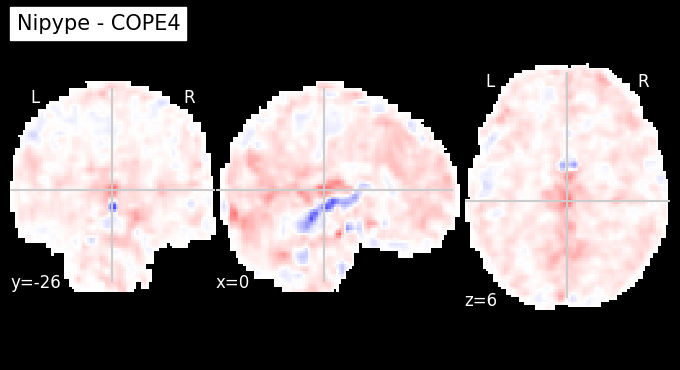

The first-level GLM#

Here we randomly choose the four copes from subject-09 run-1

plotting.plot_stat_map(nipype_cope1, bg_img=nipype_cope1, title = 'Nipype - COPE1', cmap = 'bwr', colorbar = False)

plt.show()

plotting.plot_stat_map(nipype_cope2, bg_img=nipype_cope1, title = 'Nipype - COPE2', cmap = 'bwr', colorbar = False)

plotting.plot_stat_map(nipype_cope3, bg_img=nipype_cope1, title = 'Nipype - COPE3', cmap = 'bwr', colorbar = False)

plotting.plot_stat_map(nipype_cope4, bg_img=nipype_cope1, title = 'Nipype - COPE4', cmap = 'bwr', colorbar = False)

../../_images/a7f7f387884673a96e62aa7d2d938a6b6487846759bc4500b6d0cff677c7358d.png ../../_images/bc743ce13891ebab23c9f6c7d4d668db8d11c9409d4f6e4580f7d63b35ecdb77.png ../../_images/228b3b22c00177a8ad5dc1793cbbc90dbfb495735196a4af47e73b899de0ca82.png ../../_images/babe8f68f0856f0f1608dfe550483d8ca862aae33a659d1f970a9fbe726f3bb1.png